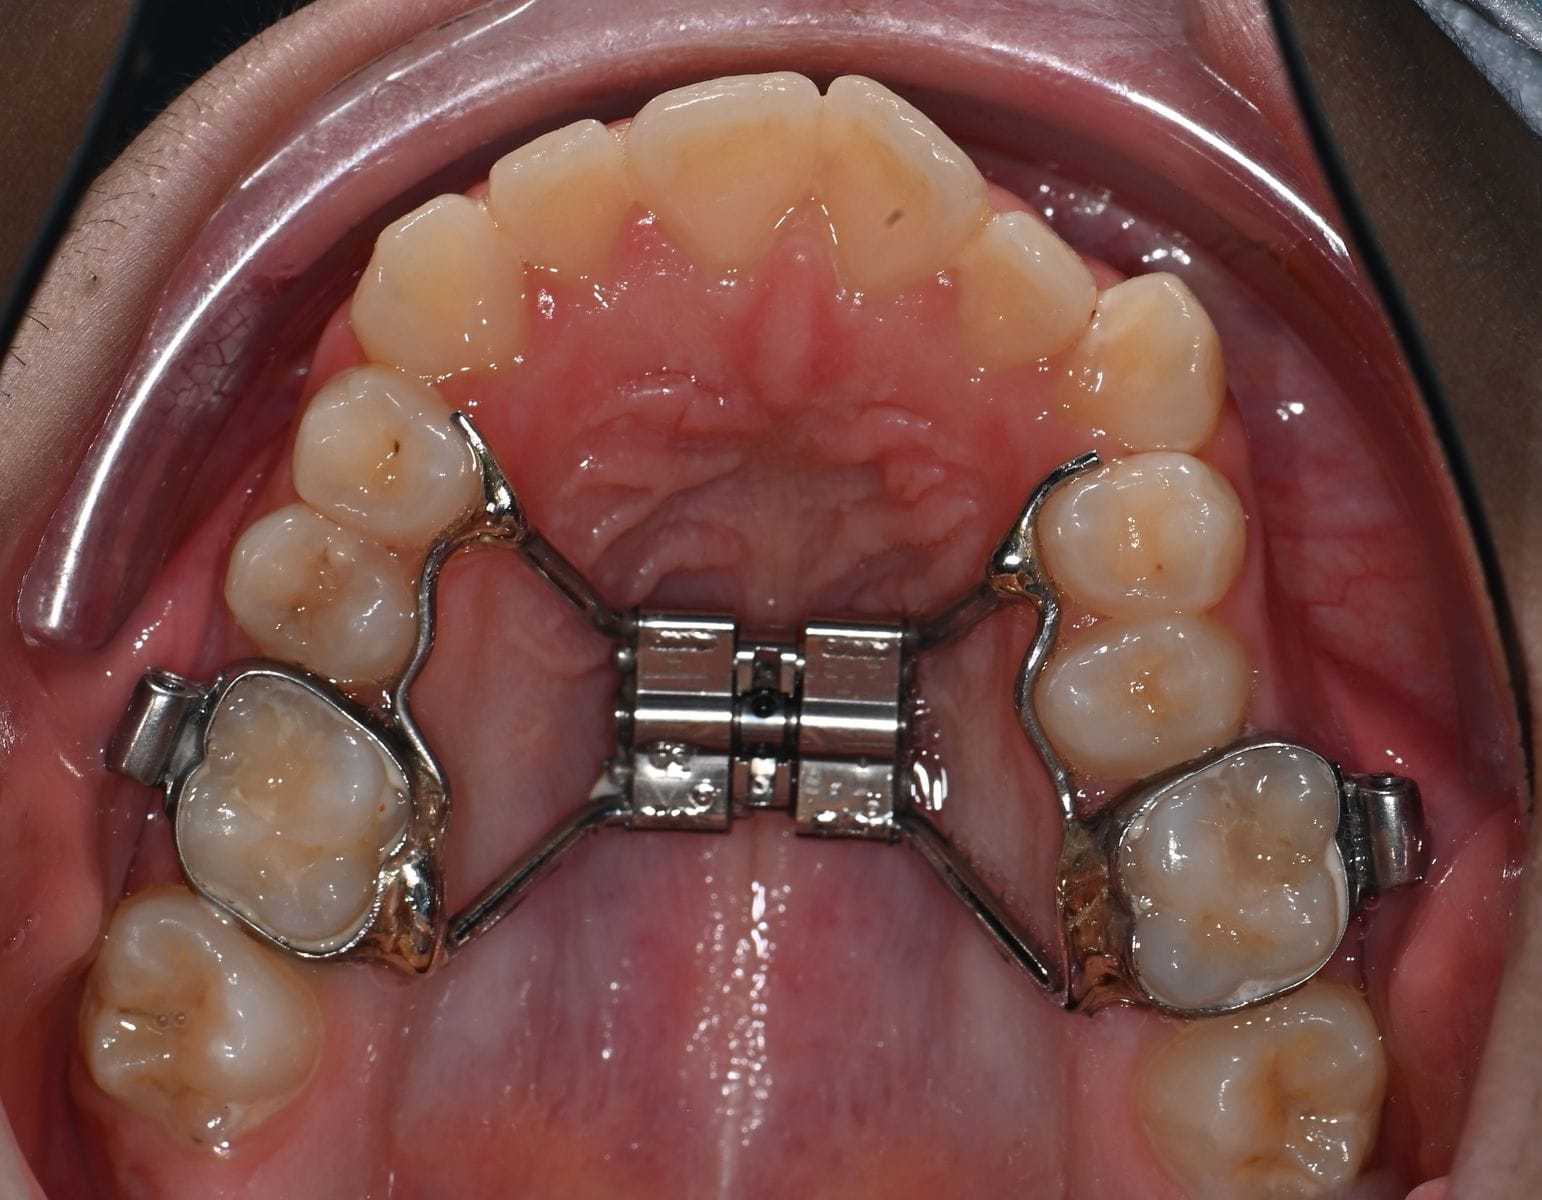

The mechanism of this device based on pushing the posterior teeth with their supporting bone laterally, which lead to correction of the bite in the posterior area of the jaw and lead to expanding upper jaw transversely and create extra space to align crowded teeth. Also, Expansion of upper jaw has a positive effect on breathing, because it lead to expand upper nasal passages

There are several designs for this appliance , most of them work in the same concept, but differ in small details

Expansion process accomplished by the parents or any other adults in the home on daily basis. Patient will feel some discomfort at the beginning during expansion , and he or she may feel a pressure around the nose and on the posterior teeth. Mild analgesics will be more than enough to eliminate any discomfort. You can watch a video on our website explain the expansion procedure.